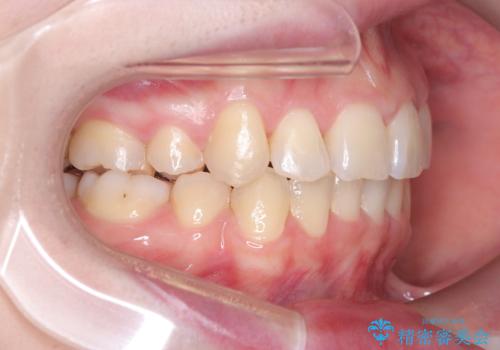

- 患者様は、結婚式までに歯並びを整えたいとのご要望で来院されました。診断の結果、上下左右の第一小臼歯を抜歯し、歯列全体を整える計画としました。審美性を重視し、目立ちにくいホワイトワイヤーを使用した矯正を提案しました。治療期間は2年を目安とし、結婚式までに前歯の整列と噛み合わせを優先的に整えるスケジュールで進めました。定期的な調整と経過観察を通じて、計画的に治療を進めました。

結婚式までに仕上げるため、通常よりも細かく調整を行い、歯の動きを効率的に管理しました。審美ワイヤーを使用したことで、治療中も目立ちにくく、写真撮影などの日常生活での見た目の負担を軽減しました。抜歯部分のスペースを閉じる際には、前歯の位置や噛み合わせのバランスに配慮し、過度な力がかからないよう進めました。患者様の大切なイベントに間に合うよう治療計画を立て、理想的な仕上がりを実現しました。